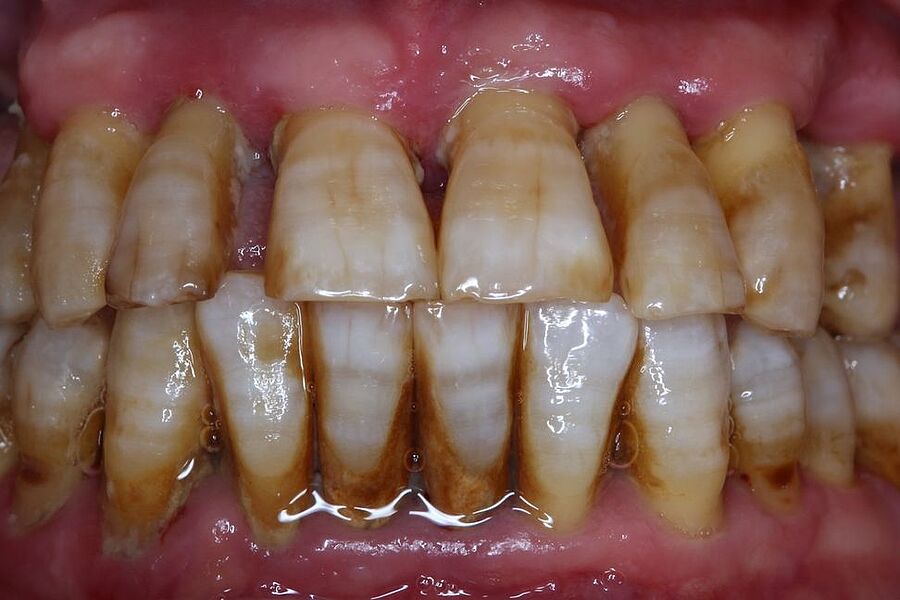

Vom 15.-18. Juni 2022 fand in Kopenhagen/Dänemark einer der weltweit führenden Kongresse in der Parodontologie, die EuroPerio10, statt. Mit einer Posterpräsentation waren Frau Dr. Rahim-Wöstefeld aus Mannheim und Frau Prof. Pretzl von der Akademie für Zahnärztliche Fortbildung Karlsruhe vertreten. Gezeigt wurde ein eindrücklicher Behandlungsfall mit einer Patientin mit einer Parodontitis im Stadium IV und gleichzeitig gestörter Kaufunktion sowie tiefem Biss.

Ein 34-jähriger Patient hatte die häusliche Mundhygiene ohne erkennbare Gründe fast vollkommen eingestellt. Die daraus resultierende desolate orale Gesamtsituation war mit seinem äußeren Erscheinungsbild und seinem sozialen Status nicht vereinbar. Aufgrund dieser Widersprüche erfolgte eine intensive Abwägung der Therapieoptionen.